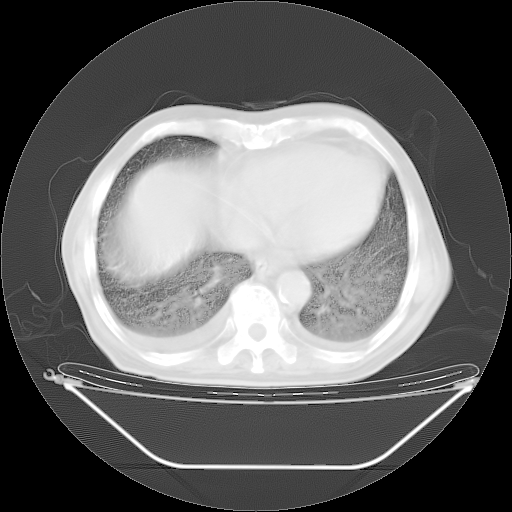

今天复查肺部CT,发现双肺广泛磨玻璃样改变。所以我把3月19日和5月9日相隔50天的肺部CT上传。请大家会诊。

5月9日肺部CT(在4月27日齐鲁医院肺部CT描述部分肺组织磨玻璃样改变,12天后肺组织广泛磨玻璃样改变)

大致读了系列胸部CT:纵隔窗无明显异常,肺窗:从4、27至今:主要是双肺中下野外带可见毛玻璃样改变,目前处于急性肺泡炎阶段,至于原因考虑1、结替组织或胶原血管性疾病所致?2、恶性疾病如恶组在肺部所致的表现或细支气管肺泡癌?3、药物或其它原因如肺蛋白沉着症所致肺泡炎目前不太可能?总之,明天就去请我院的呼吸科、感染科、血液科和临免专家会诊哈。